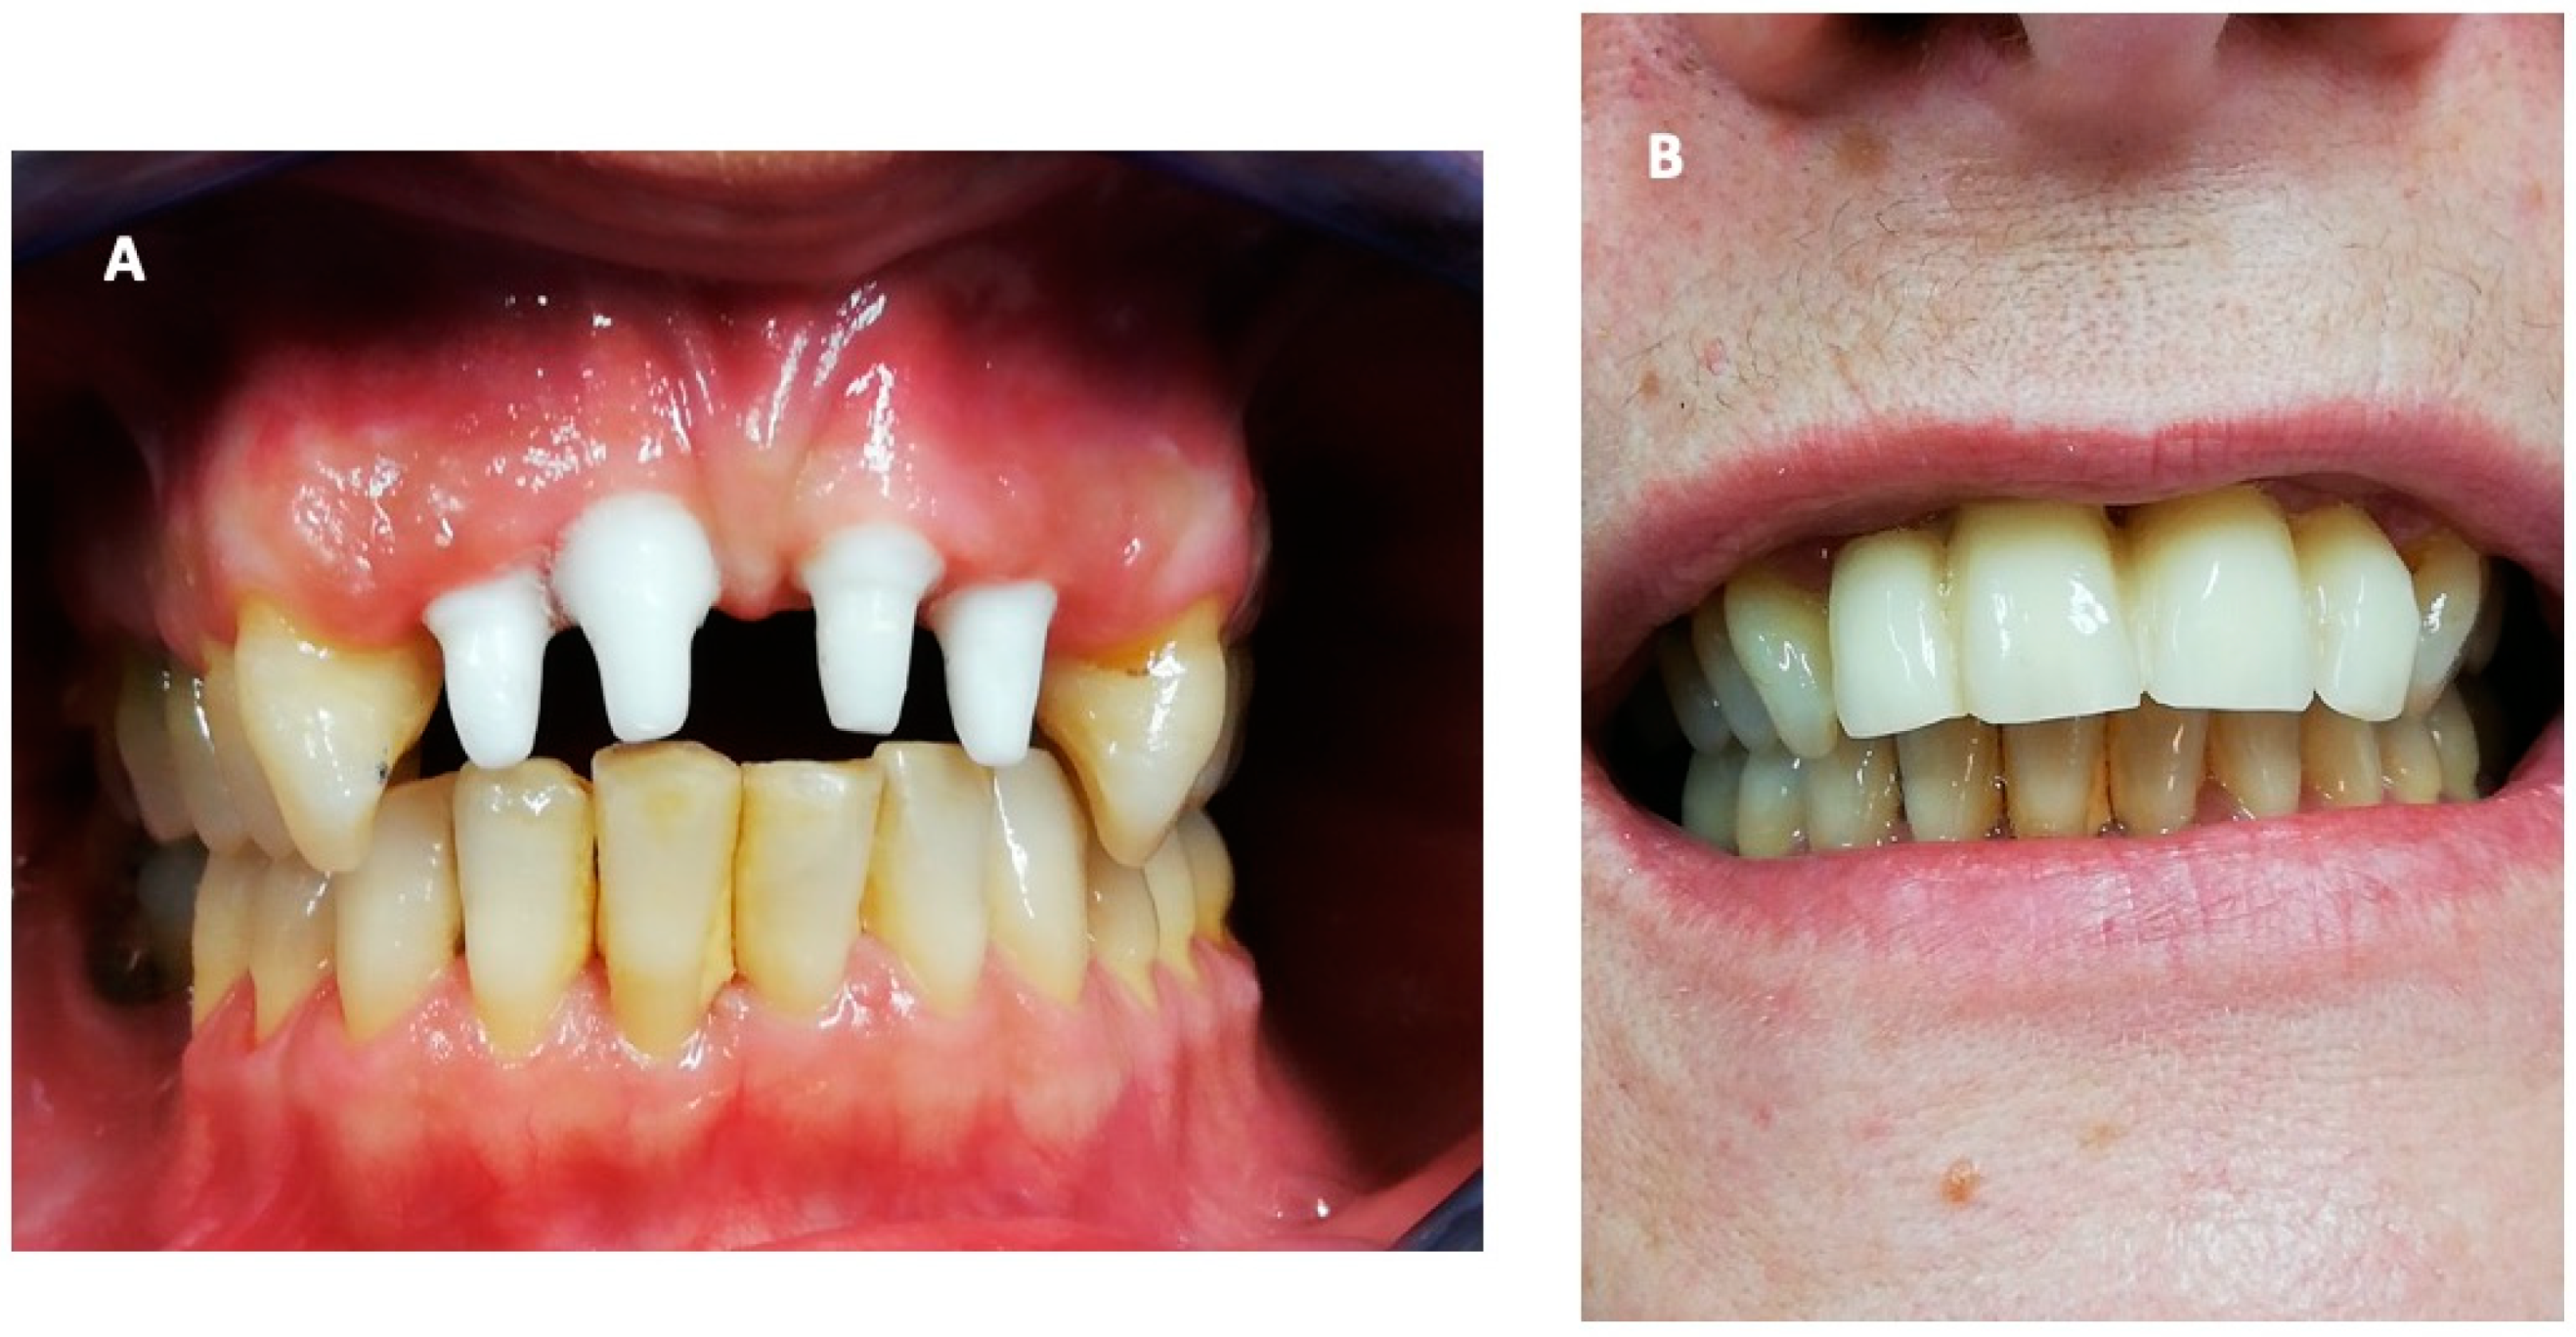

2. Case Report